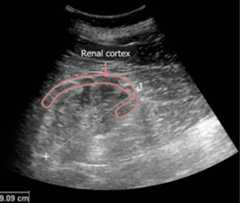

Ultrasound imaging

SometimespatientsPatientsIndividuals participating in the health care system for the purpose of receiving therapeutic, diagnostic, or preventive procedures.Clinician–Patient Relationship with CKD will have a normalGFRGFRThe volume of water filtered out of plasma through glomerular capillary walls into Bowman’s capsules per unit of time. It is considered to be equivalent to inulin clearance.Kidney Function Tests, but ultrasound findings will be consistent with CKD. ThesepatientsPatientsIndividuals participating in the health care system for the purpose of receiving therapeutic, diagnostic, or preventive procedures.Clinician–Patient Relationship are at high risk for developing a ↓GFRGFRThe volume of water filtered out of plasma through glomerular capillary walls into Bowman’s capsules per unit of time. It is considered to be equivalent to inulin clearance.Kidney Function Tests if their disease progresses. Ultrasound findings consistent with CKD include:

• PolycystickidneysKidneysThe kidneys are a pair of bean-shaped organs located retroperitoneally against the posterior wall of the abdomen on either side of the spine. As part of the urinary tract, the kidneys are responsible for blood filtration and excretion of water-soluble waste in the urine.Kidneys: Anatomy

• ChronichydronephrosisHydronephrosisHydronephrosis is dilation of the renal collecting system as a result of the obstruction of urine outflow. Hydronephrosis can be unilateral or bilateral. Nephrolithiasis is the most common cause of hydronephrosis in young adults, while prostatic hyperplasia and neoplasm are seen in older patients.Hydronephrosis

• Small, echogenickidneysKidneysThe kidneys are a pair of bean-shaped organs located retroperitoneally against the posterior wall of the abdomen on either side of the spine. As part of the urinary tract, the kidneys are responsible for blood filtration and excretion of water-soluble waste in the urine.Kidneys: Anatomy with thin cortices

Hydronephrosis on renal ultrasound

Image: “Hydro” by morning2k. License:CC BY-SA 3.0, edited by Lecturio.